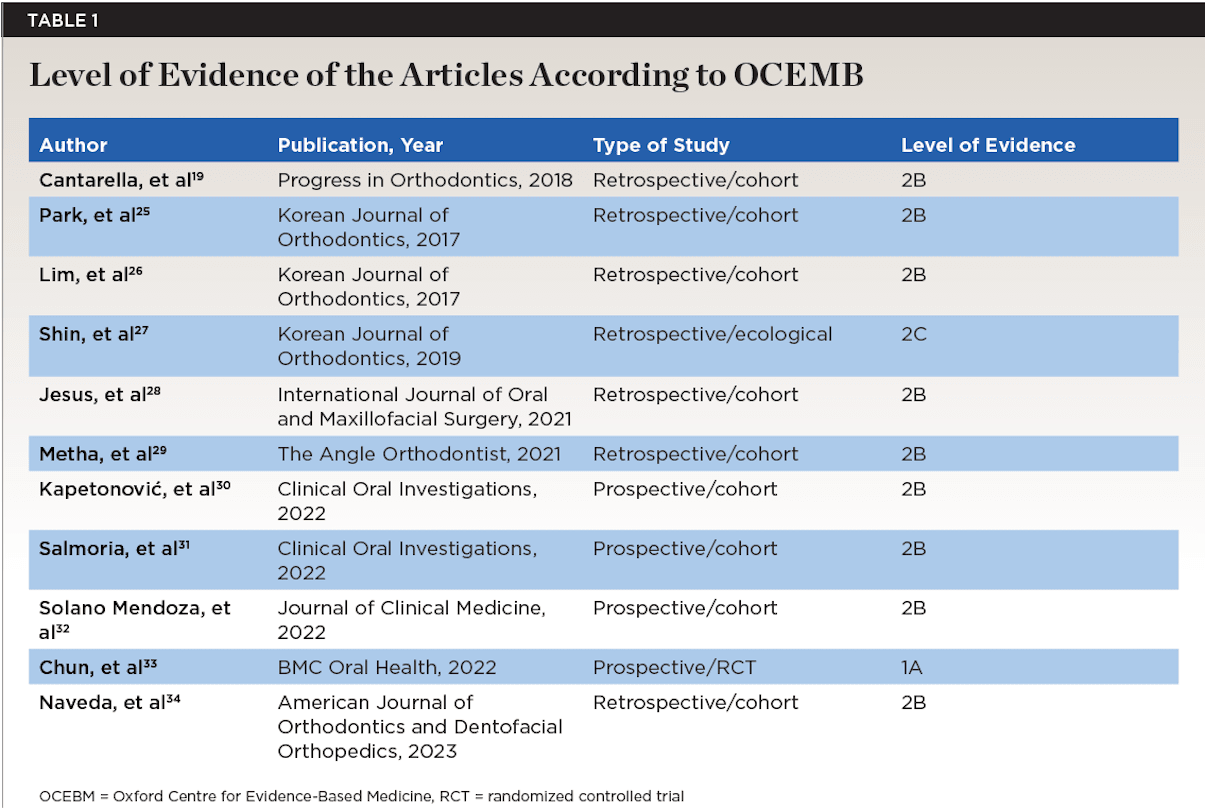

The data collected from each study selected for the systematic review included: author, journal and year of publication, and type of study in order to determine the level of evidence of these articles using the classification of the Oxford Centre for Evidence-Based Medicine (OCEBM).24 The articles selected are listed in

Table 1.19,25-34

Upon reviewing the remaining 52 articles, 41 were excluded due to lack of scientific evidence, as they either were case reports or lacked conclusive findings. Therefore, the articles included in the present review amounted to 11 total, with a moderate-to-high level of evidence and a moderate-to-low risk of bias, as reflected in Table 1 and Table 2, respectively.

Level of Evidence

The OCEBM classification assesses the level of evidence according to each clinical setting.24 The present systematic review has a “moderate level of evidence and strength of recommendation” (Table 1).